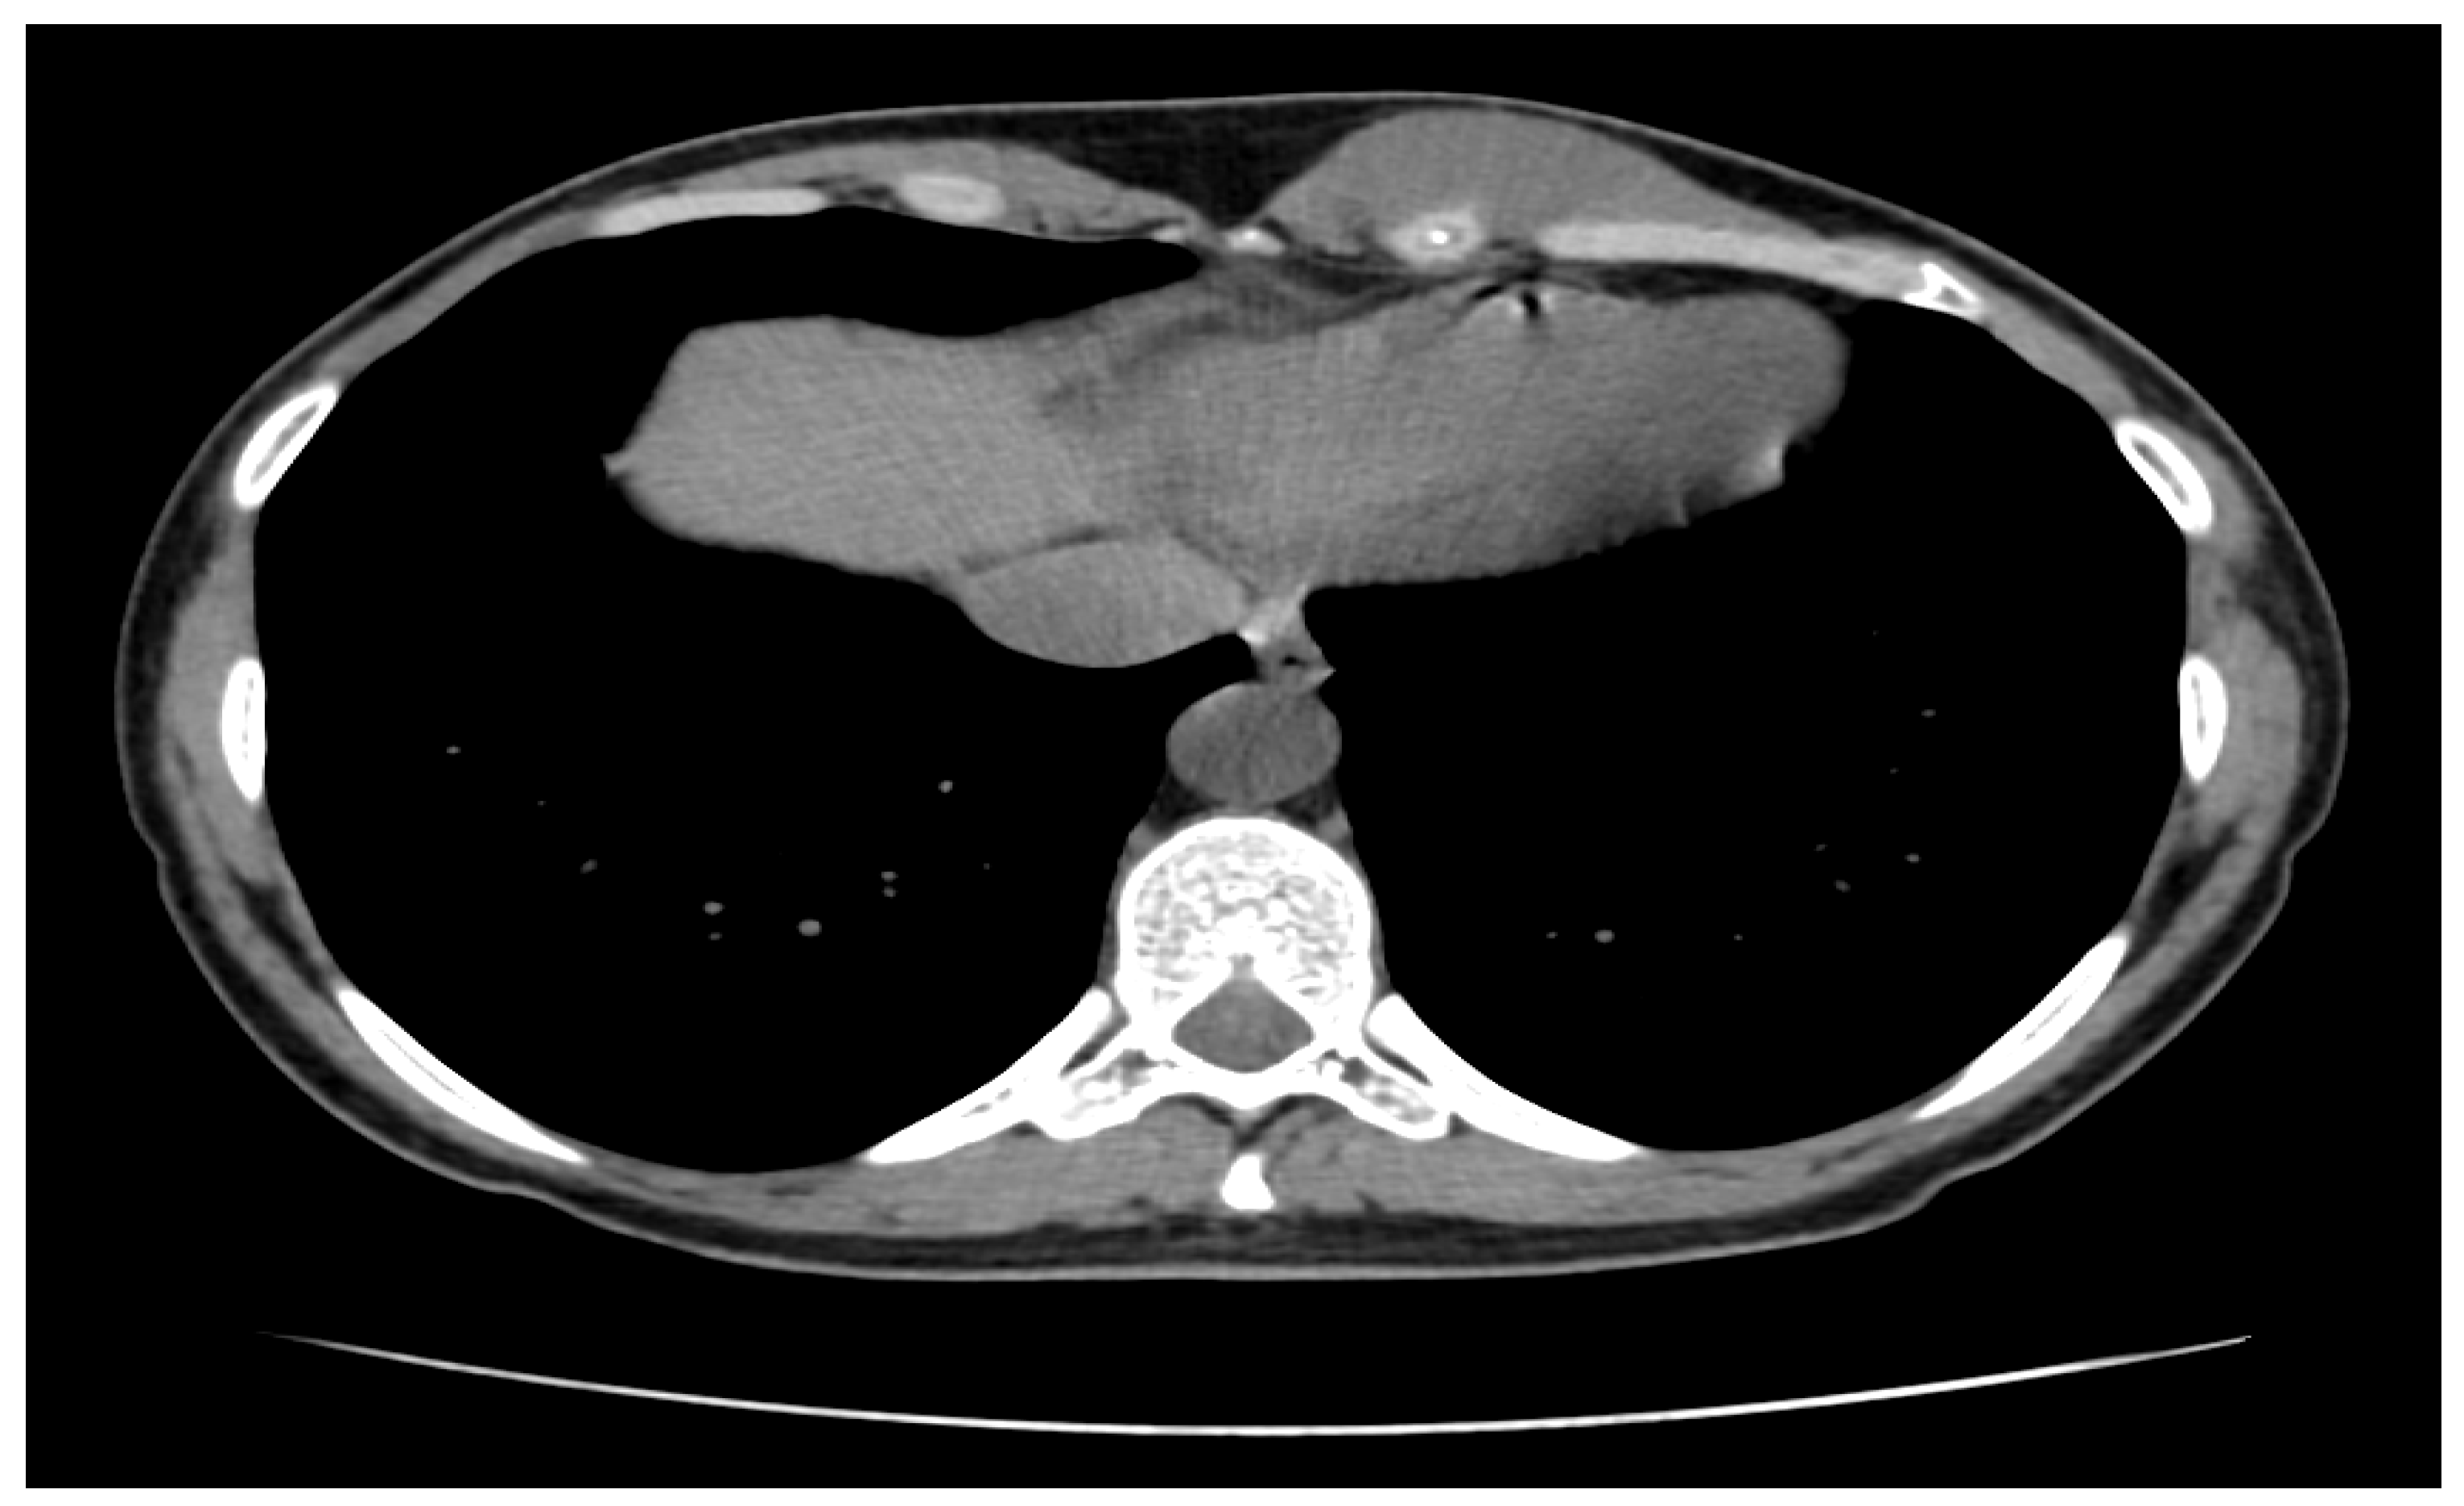

2.1. Initial Diagnostic Workup

3.1. Diagnosis and Imaging Characteristics